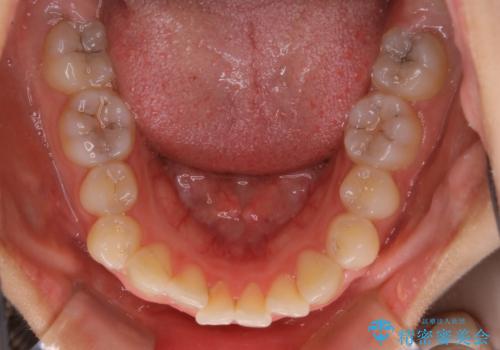

前歯のがたつきをインビザラインで治療

- 上下前歯のがたつきが気になるとの事で来院された患者様です。がたつきの程度が軽度であったため、インビザラインライトにて治療をおこないました。

がたつきの程度が軽度であったことと、インビザラインを正しく装着して頂けたことで短期間で治療終了することが出来ました。